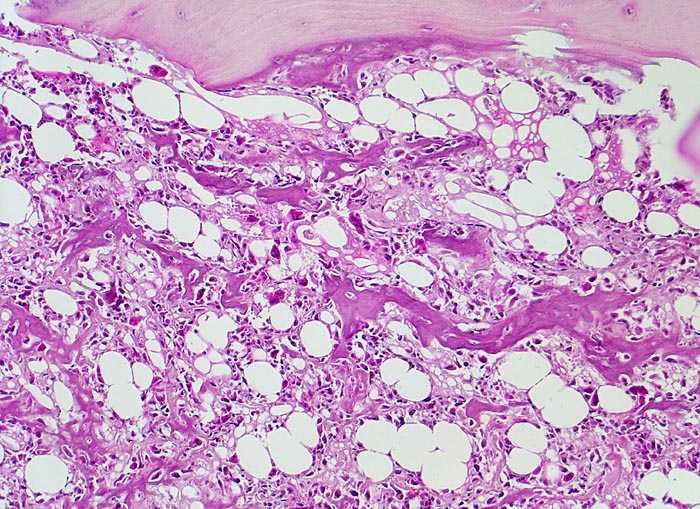

Osteosarkom

Atypische Tumorzellen bilden fein verzweigtes verkalktes Osteoid im ehemaligen Markraum. Neben den Tumorzellen mehrkernige reaktive osteoklastäre Riesenzellen. Oben im Bild erhaltener nicht maligner Lamellenknochen.

16 jähriger Jugendlicher mit seit mehreren Wochen bestehenden belastungsunabhängigen Schmerzen im distalen Femur rechts oberhalb des Knies (Metaphyse). Im Röntgenbild irreguläre Verdichtung, zum Teil auch Aufhellung der ursprünglichen Knochenstruktur mit Zerstörung der Corticalis und spiculaartige (=sonnenstrahlenähnliche) Periostreaktion. Im Serum erhöhte alkalische Phosphatase.